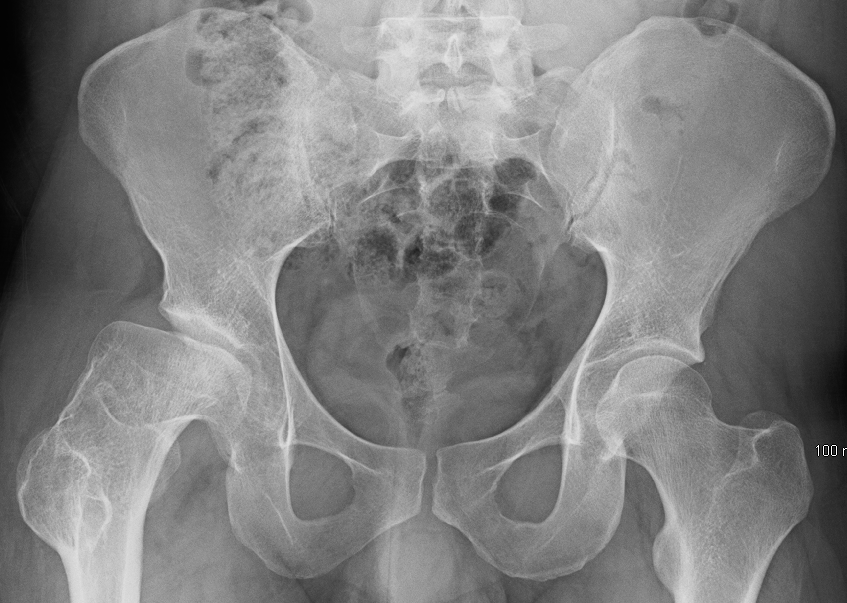

엑스레이 촬영을 통해 진단을 확인할 수 있다.[1] X-ray는 일반적으로 편평해지고, 이후 조각난 대퇴골두를 보여준다.[1] 엑스레이가 불확실한 경우, 뼈 스캔이나 MRI가 진단에 유용할 수 있다.[1] 일반적으로 단순 방사선 사진의 변화는 임상 증상 발현으로부터 6주 이상 지연되므로, 조기 진단을 위해 골 신티그래피와 MRI가 시행된다.[1] MRI 결과는 단순 방사선 촬영에서 88~93%에 비해 97~99%로 더 정확하다.[1] MRI 또는 뼈 스캔이 필요한 경우, 긍정적인 진단은 대퇴골두 골단(발달 중인 대퇴골두)의 혈관 분포의 불균일한 영역에 의존한다.[1]

레그-칼베-페르테스 병으로 인한 오른쪽 고관절 변형 엑스레이 (엑스레이의 왼쪽)